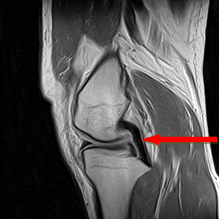

전방십자인대 손상

| 정상 전방십자인대 |

파열된 전방십자인대 |

| 굵고 검은 힘줄이 좌측 하방에서 우측 상방으로 쫙 뻗어있는 모습을 볼수 있다. |

하얀 것은 관절액의 모습으로 전방십자인대의 위치뿐 아니라, 관절내의 다른 곳도 채우고 있는 모습을 볼 수 있다. |